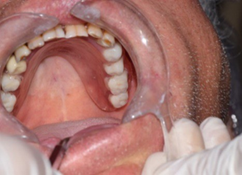

Examination of the mucosa around the dental socket showed the absence of attached gingiva (Figure 3). OAC closure was performed at the same day under local anaesthesia. The patient underwent extraoral antisepsis with povidone iodine solution and intraoral antisepsis with chlorhexidine 0.12%. Infiltration anaesthesia was performed around the dental socket and palate using 4% articaine and epinephrine 1: 100,000.

Irrigation of the sinus with saline through the OAC was carried out. Lavage fluid was clear and did not contain inflammatory exudates. A rectangular gingival flap of total thickness (Figure 4) was raised from the top of the ridge, rotated and buccally sutured to gain attached gingiva (Figure 5).